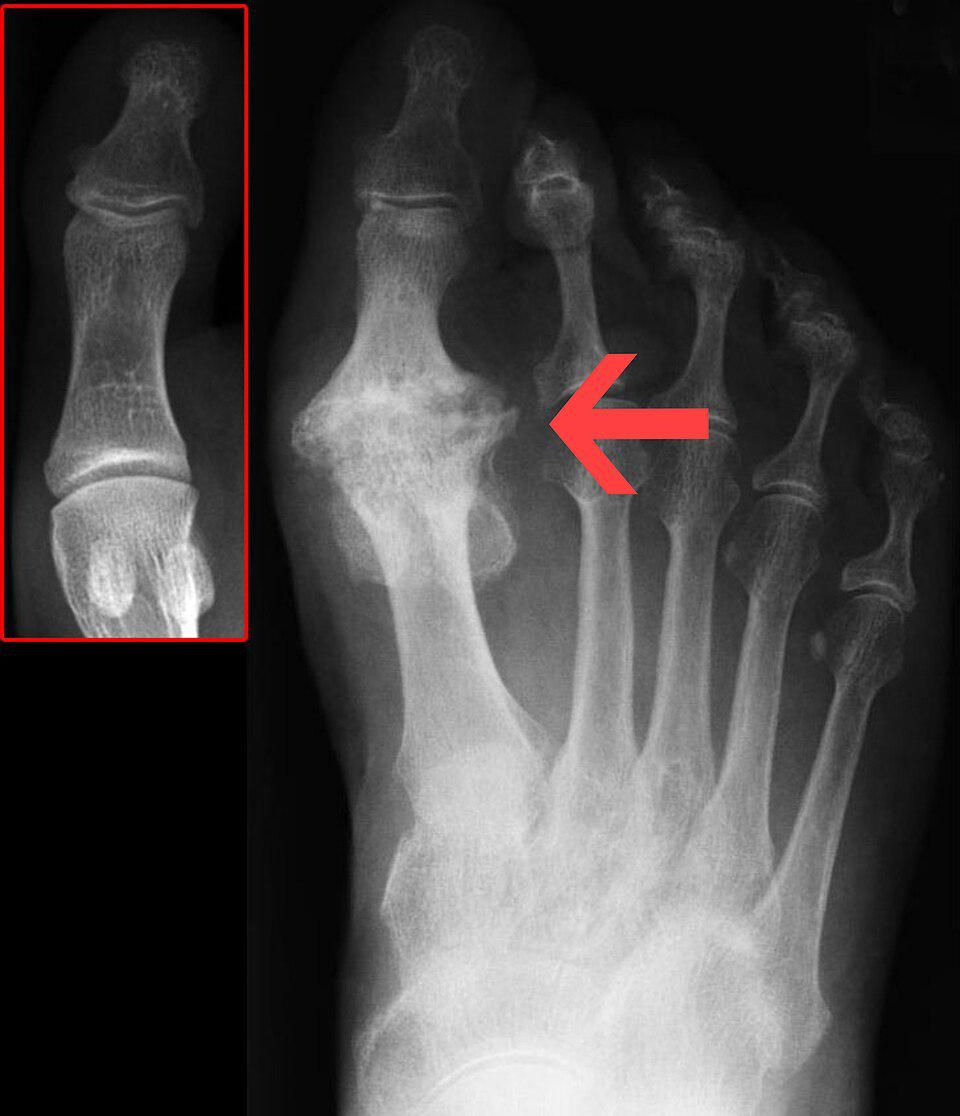

3. Metatarsalgia

Metatarsalgia adalah nyeri pada bola kaki tempat lima tulang metatarsal berada. Metatarsal membantu membentuk lengkungan kaki, yang penting untuk aktivitas berjalan dan menahan beban.

Nyeri metatarsalgia sering digambarkan sebagai nyeri yang tajam atau terbakar. Kondisi ini bisa memburuk saat kamu berdiri, berlari, berjalan, atau melenturkan kaki.

Pelari dapat mengalami artritis pada sendi mana pun di kaki, tetapi artritis ini sangat umum terjadi di sepanjang kepala dan pangkal tulang metatarsal. Karena artritis terjadi akibat degenerasi akibat akumulasi keausan, pelari yang lebih tua lebih rentan terhadap artritis.

Artritis di kaki adalah kondisi kronis yang berkembang perlahan seiring waktu. Kondisi ini jarang terjadi secara tiba-tiba kecuali terjadi cedera traumatis (seperti fraktur Lisfranc).

9. Hallux rigidus

Hallux rigidus, atau jempol kaki kaku, adalah bentuk artritis degeneratif yang dapat menyebabkan ketidaknyamanan yang signifikan.

Kondisi ini terutama memengaruhi sendi metatarsophalangeal, yang menghubungkan jempol kaki dengan bagian kaki lainnya.

Sendi ini sangat penting untuk berjalan dan berlari, dan penggunaan berlebihan atau cedera dapat mengakibatkan kondisi yang menyakitkan hallux rigidus.